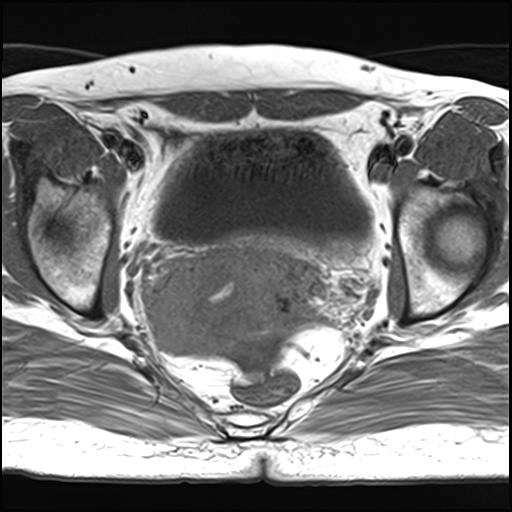

Dị dạng động tĩnh mạch tử cung (Uterine Arteriovenous Malformation - AVM)